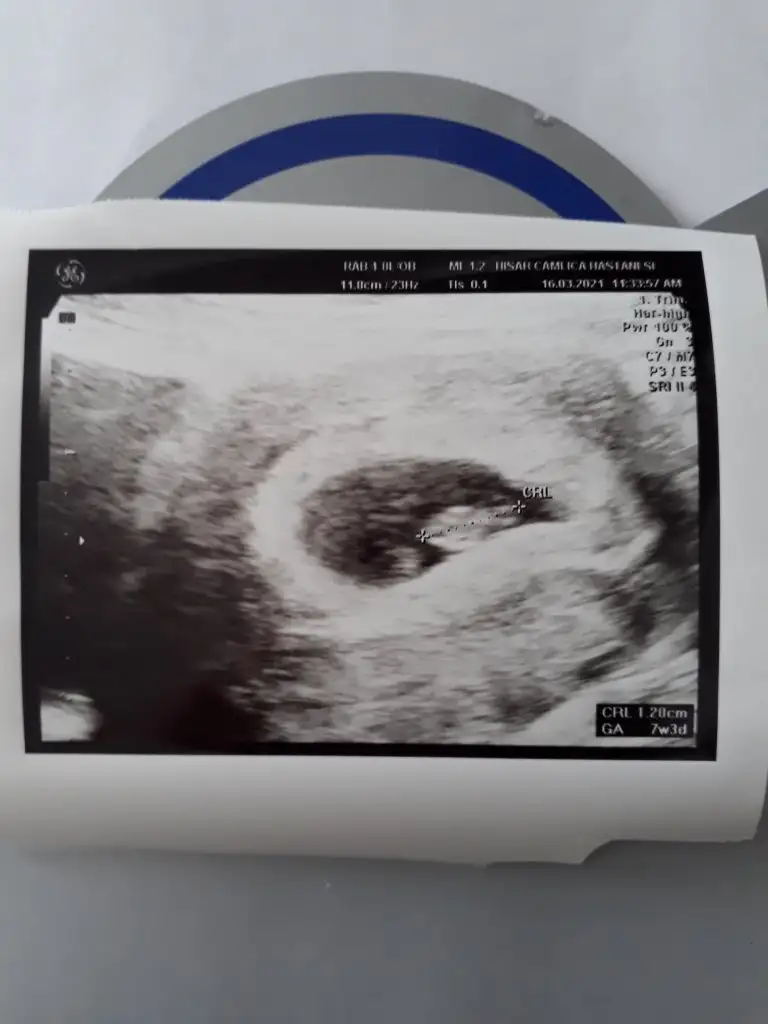

evet ilk oğlumu sonra kızımı dogru tahmin etmiştiniz simdi de supriz bebeğimizi sorayim dedim sagolunErkek gibi sanki olursa 12-13 hafta paylaşın sizinmi kızınız vardı dimi![]()

Anladm cok teşekkür ederimYok tatlım bebegin alt bölgesini almamış USG![]()

Erkek sanki emin olamadım başka USG varsa paylaşın